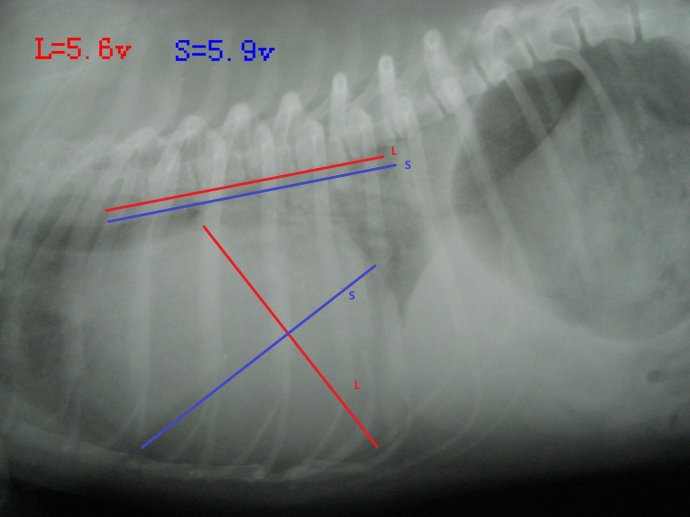

这是一只京巴犬,因为剧烈咳嗽而就诊,经检查确诊为心衰。

如上图,VHS=5.6v+5.9v=11.5v